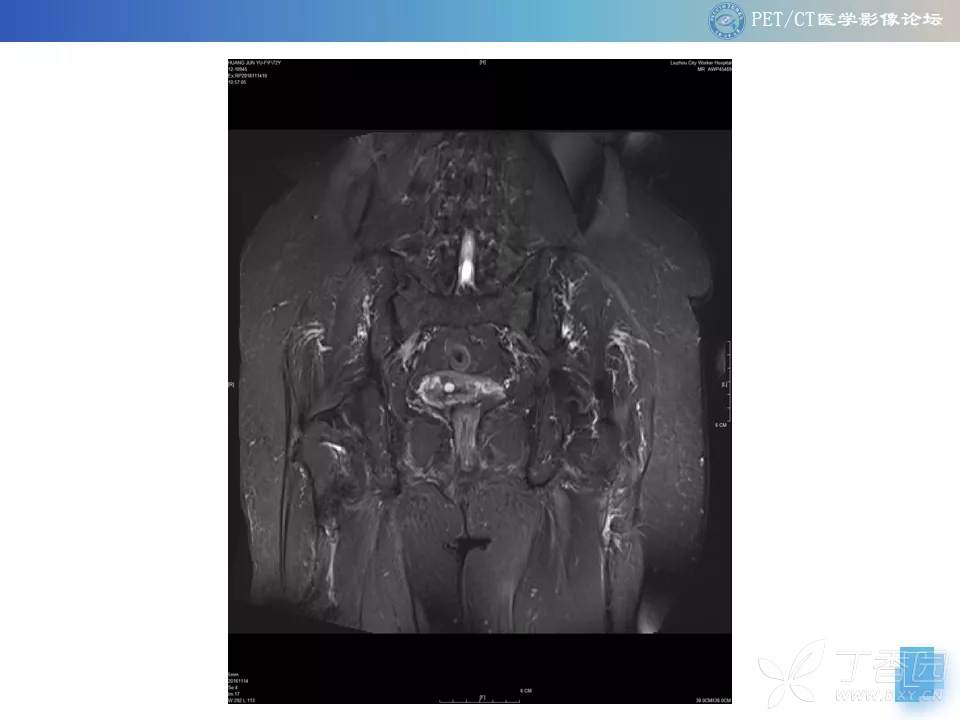

【PET/CT 病例读片】髋关节占位性病变

注:病例来源【PETCT病例读片第二十二期】

查看病例结果及诊断分析请关注公众号【PETCT医学影像论坛】